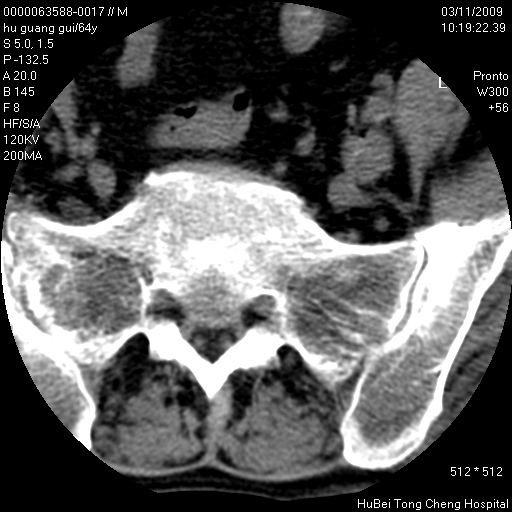

患者 男,64岁。腰痛十余天。(临床未提供其他病史)

临床诊断:腰痛原因待查(腰椎间盘突出症?)。

腰椎间盘ct轴位平扫(层厚5mm,层距4mm),图像如下:

右侧骶骨侧块骨侵蚀,骶髂关节骨性关节面破坏,并见软组织肿块,考虑骨转移瘤可能,进一步检查。

1.腰椎退行性变,腰4—5椎间盘膨出。

2.右侧骶骨侧块骨侵蚀,骶髂关节骨性关节面破坏,并见软组织肿块,考虑:脊索瘤,骨转移瘤可能,进一步检查。

1)腰椎退行性变,l4—5椎间盘膨出。2)骶骨右侧块骨转移瘤可能,3)水平骶椎。建议作一步检查。